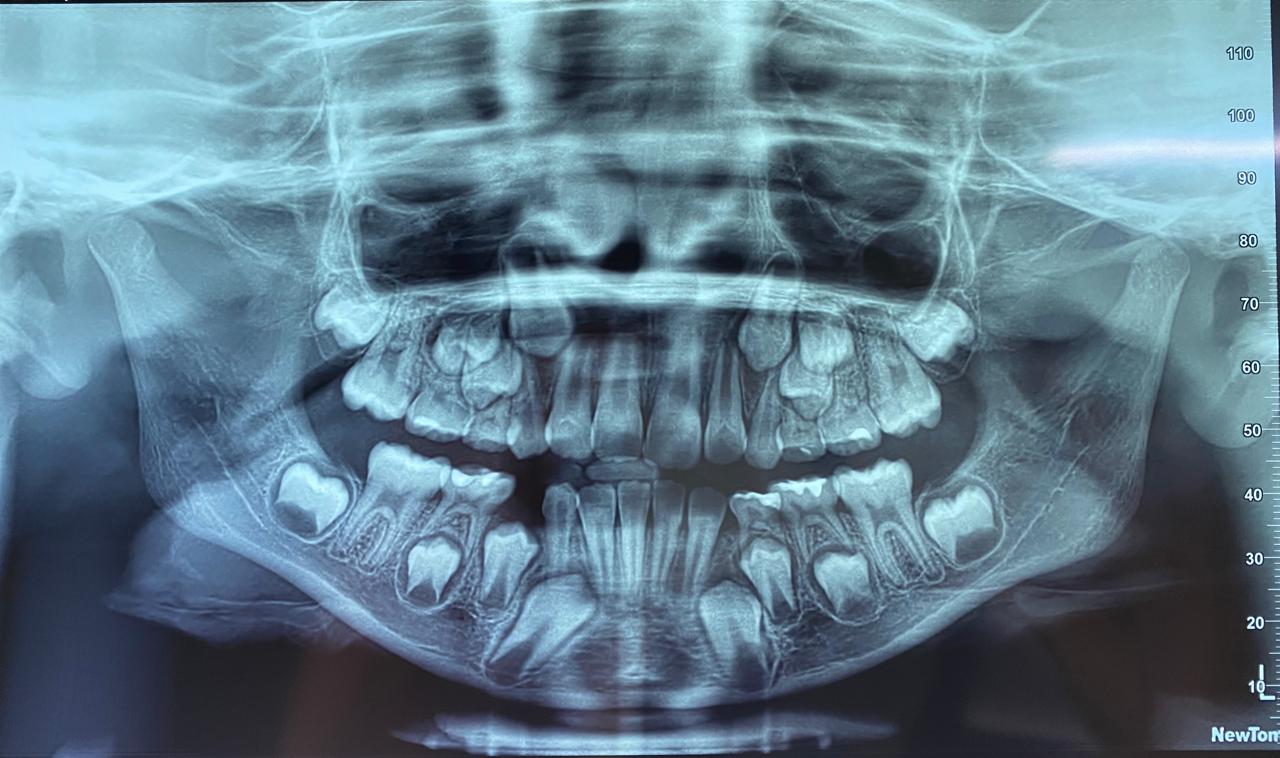

La mejor forma de conocer si tus dientes necesitan un tratamiento ortodóncico es agendar una consulta con nuestros especialistas para realizar el diagnostico correspondiente. A través del diagnóstico obtendremos elementos indispensables para determinar el tipo de tratamiento, duración y consideraciones generales como la historia clínica y odontológica del paciente, la realización de modelos en yeso de los dientes, radiografías y fotografías. En función de los resultados que arroje el estudio, desarrollaremos un plan de tratamiento de acuerdo con tus características y necesidades.